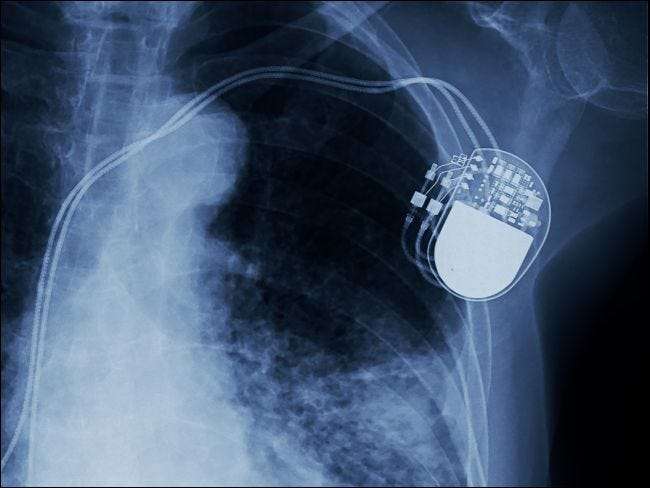

Czy naprawdę można zhakować rozruszniki serca (i inne urządzenia medyczne)?

Od rozruszników serca po smartwatche, w coraz większym stopniu stajemy się gatunkiem cybernetycznym. Dlatego ostatnie nagłówki o lukach w zabezpieczeniach wszczepionych urządzeń medycznych mogą wywołać dzwonki alarmowe. Czy naprawdę można zhakować rozrusznik serca Twojego dziadka, a jeśli tak, jakie jest rzeczywiste ryzyko?

To aktualne pytanie. Tak, nadchodzą znaczące zmiany w technologii medycznej - urządzenia wszczepialne mogą teraz komunikować się bezprzewodowo, a nadchodzący medyczny Internet rzeczy (IoT) przynosi ze sobą różne urządzenia do noszenia, aby zapewnić lepszą łączność lekarzom i pacjentom. Jednak jeden z głównych producentów urządzeń medycznych trafił na pierwsze strony gazet z nie jedną, ale dwoma krytycznymi lukami w zabezpieczeniach.

W marcu Departament Bezpieczeństwa Wewnętrznego ostrzegł to hakerzy mogli uzyskać bezprzewodowy dostęp do wszczepionych rozruszników serca firmy Medtronic . Następnie, zaledwie trzy miesiące później, Firma Medtronic dobrowolnie wycofała niektóre ze swoich pomp insulinowych z podobnych powodów.

Z pozoru jest to przerażające, ale może nie być tak złe, jak się wydaje. Hakerzy nie mają dostępu do wszczepionych rozruszników serca z odległych terminali oddalonych o setki mil ani nie mogą przeprowadzać ataków na szeroką skalę. Aby zhakować jeden z tych rozruszników, atak musi zostać przeprowadzony w bliskiej fizycznej odległości od ofiary (w zasięgu Bluetooth) i tylko wtedy, gdy urządzenie łączy się z Internetem w celu wysyłania i odbierania danych.

Chociaż mało prawdopodobne, ryzyko jest realne. Firma Medtronic zaprojektowała protokół komunikacyjny urządzenia w taki sposób, aby nie wymagał on żadnego uwierzytelniania, a dane nie były szyfrowane. Zatem każdy wystarczająco zmotywowany może zmienić dane w implancie, potencjalnie modyfikując jego zachowanie w niebezpieczny lub nawet śmiertelny sposób.